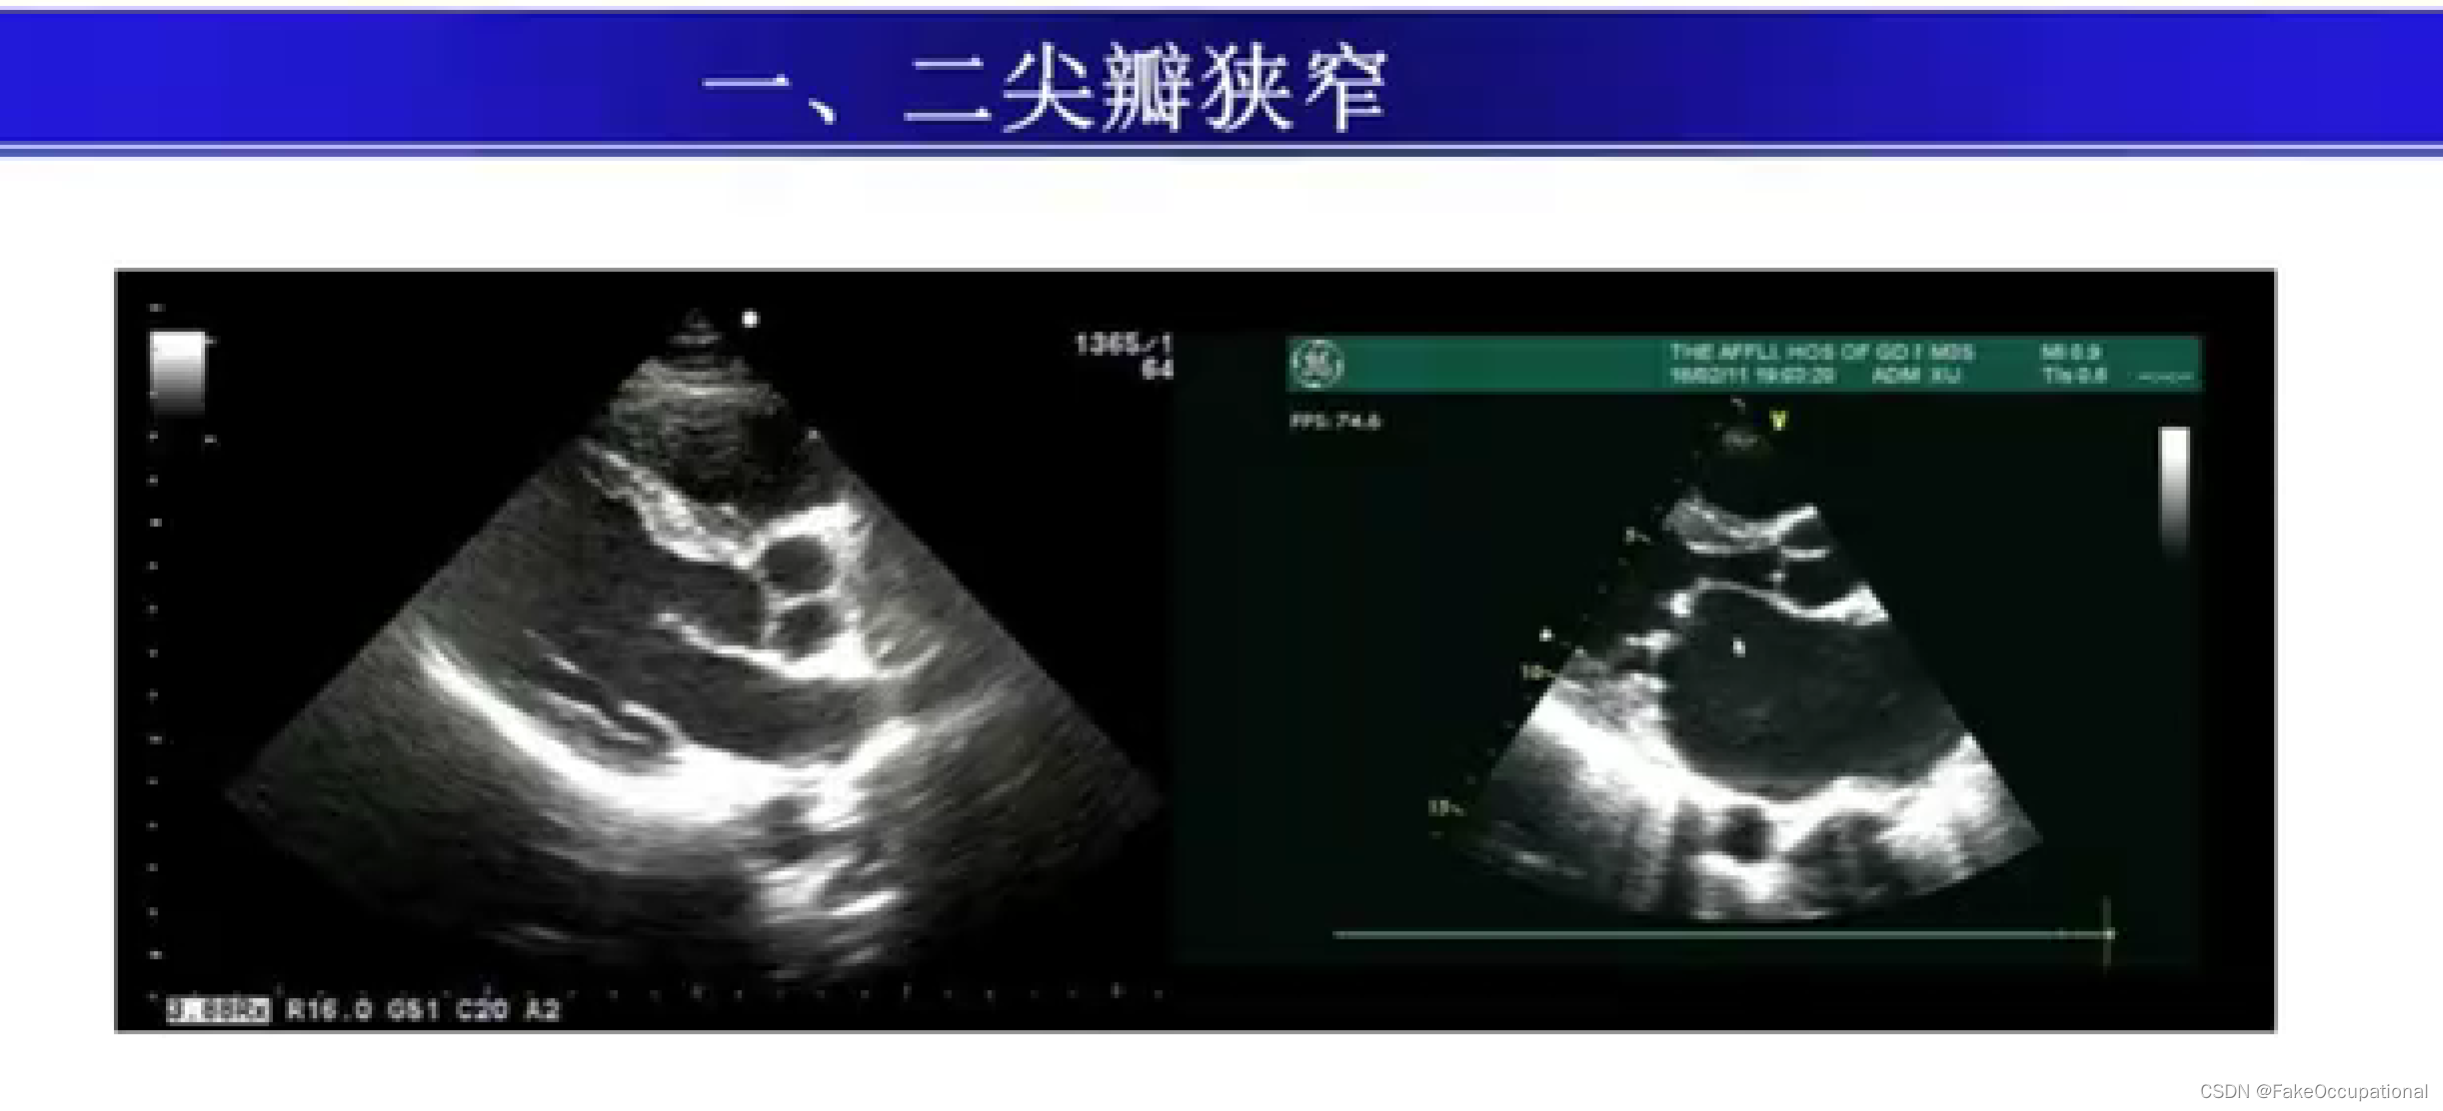

瓣膜病超声诊断